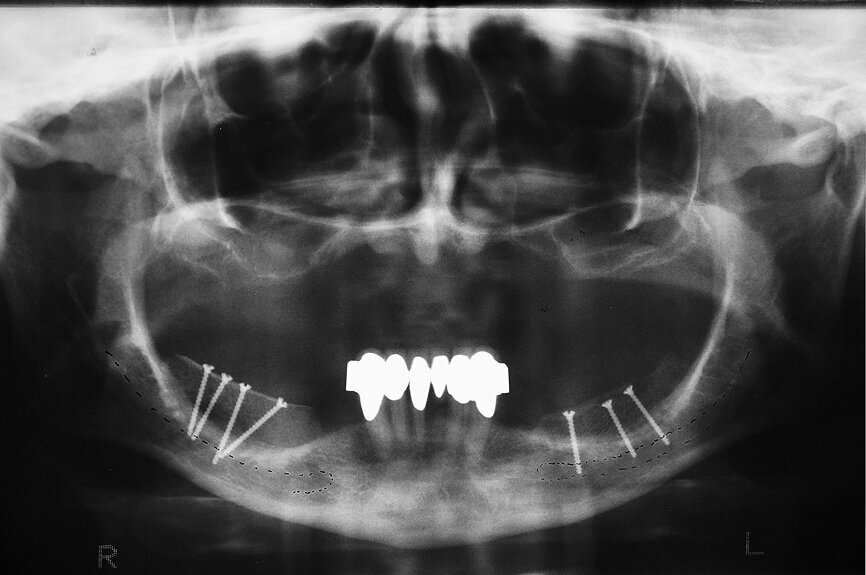

Fig. 20 : Tomographie panoramique dentaire du patient aux fins du contrôle du résultat final.

L’insertion des implants a été réalisée à l’aide de la clé à cliquet DRM et de la douille standard, avec un couple de serrage d’environ 35–45 Ncm, afin de parvenir à une stabilité primaire maximale (Fig. 17). Par la suite, les tenons pour navigation implantaire et le guide chirurgical ont été retirés du maxillaire pour y insérer les façonneurs gingivaux, avec un couple de serrage de 25 Ncm (Figs. 18 et 19). Une technique similaire a été utilisée pour la préparation des lits implantaires et l’insertion des implants dans la mandibule, ou six implants CAMLOG de 4,3 mm in diamètre et de 11,0 mm de longueur ont été insérés sous guidage total dans les sites dentaires 15, 14, 12, 22, 24 et 25. Une tomographie panoramique dentaire postopératoire a permis de visualiser les implants insérés dans le maxillaire et la mandibule (Fig. 20).

19 : Résultat de l’implantation avec tous les implants in situ.